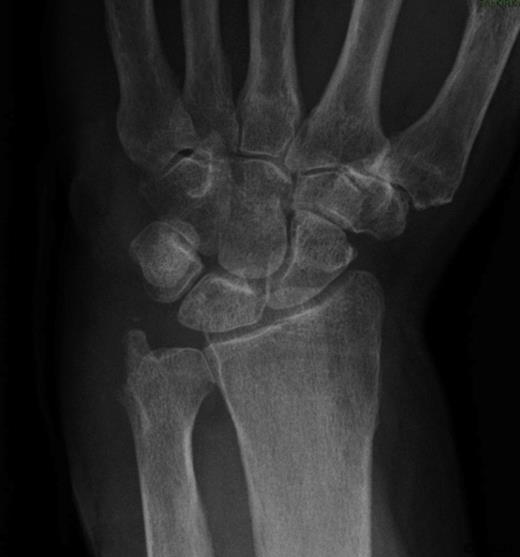

She was subsequently referred to the hand clinic. X ray this time showed destruction of the ulnar styloid consistent with a bony infection (Figure 2). MRI showed destruction localised around the ulnar head with oedematous changes extending up the shaft of the ulna (Figure 3).

AP Xray of the wrist showing destruction of the ulnar styloid consistent with a bony infection. Soft tissue swelling can also be noted over the dorsum of the wrist